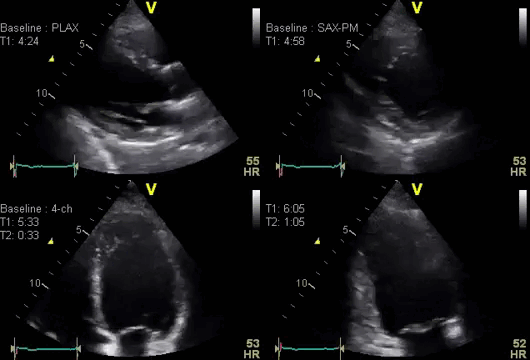

SmartStress

Автоматически корректирует параметры для оптимизации рабочего процесса, повышения воспроизводимости и диагностической достоверности.